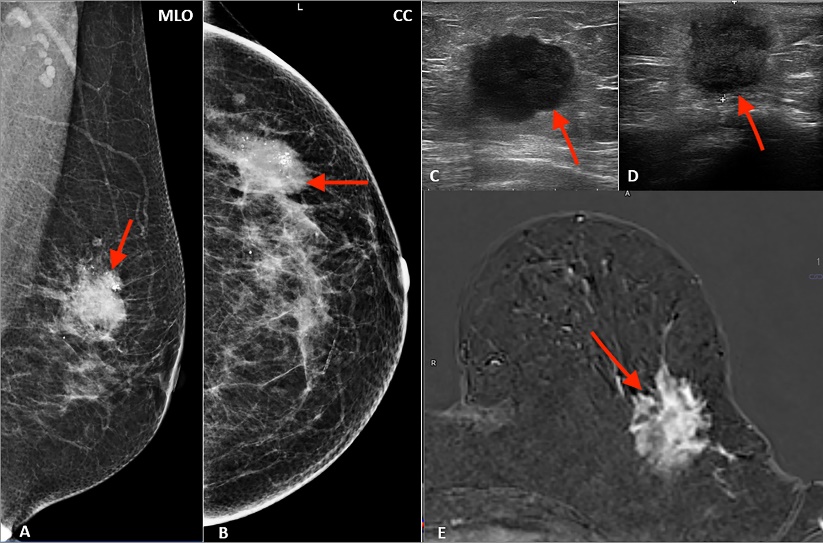

Dr. Thanga Meena is an Assistant Professor at the Barnard Institute of Radiology, Madras Medical College She has completed her MD in Radiodiagnosis at the Barnard Institute of Radiology, Madras Medical College. She has amassed over 6 years of clinical, academic, and diagnostic imaging experience contributing to both student education and patient care. Her specialized interests include Women’s Imaging, Fetal Imaging and Chest Imaging Her publications include orbital doppler study in diabetic retinopathy, Para vesical hernia as an unusual cause of closed-loop obstruction, Ectopic ureterocele with duplex kidney in adolescent girl, Lung ultrasound in pediatric pneumonia and the role of shear wave elastography in renal calculus.